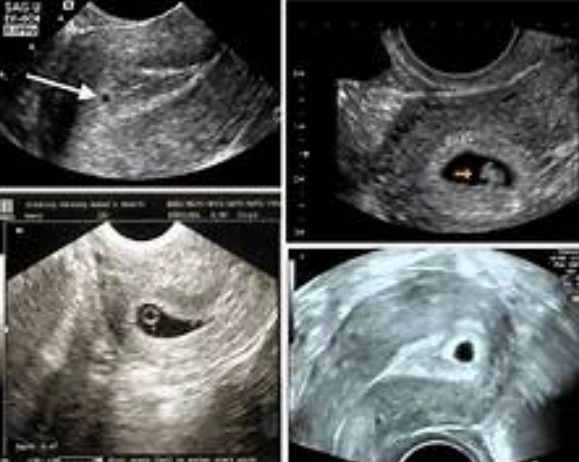

To Confirm Pregnancy Location

As mentioned, ruling out an ectopic pregnancy is a top priority. An ectopic pregnancy occurs when the embryo implants outside the uterus, usually in a fallopian tube. It's non-viable and dangerous. An ultrasound is the primary way to check the pregnancy's location.

The "There's a Concern" Scenario

This could be a few things. The sac might be seen in the wrong place (indicating a possible ectopic), or the measurements might be significantly off from your dates. If there's pain or bleeding alongside unclear findings, your doctor will discuss the next steps, which may include blood tests (to check hCG hormone levels) and close monitoring.

What if my ultrasound shows nothing at all?

First, don't panic. If you're certain of your dates and the ultrasound shows no signs of a pregnancy in the uterus, it could mean a few things: you're earlier than you think, you've miscarried very early (a chemical pregnancy), or, crucially, it could signal an ectopic pregnancy that isn't yet visible. This is why your doctor will correlate the findings with your hCG blood levels. Rising hCG with no uterine pregnancy seen is a red flag for ectopic.